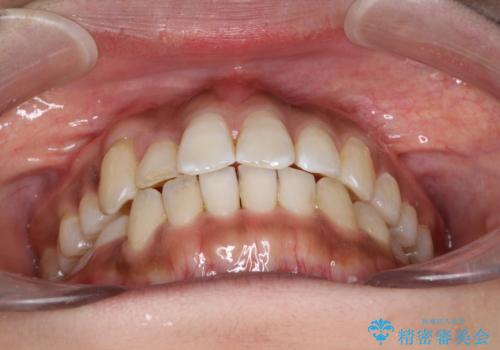

インビザラインと補助装置の併用による八重歯の抜歯矯正

- 八重歯を治したいとのことで来院されました。

重なりが強い右側の上下の歯を1本ずつ抜歯する計画としました。

インビザラインでの治療がご希望でしたが、右上の歯のかさなりが強いところは、補助装置である程度動かしてからインビザラインに移行することにしました。

下顎はインビザラインのみで治療を行いました。

インビザラインだけで歯を動かすよりも、補助装置を併用することにより効率的に、短期間で治療を行うことができる場合があります。